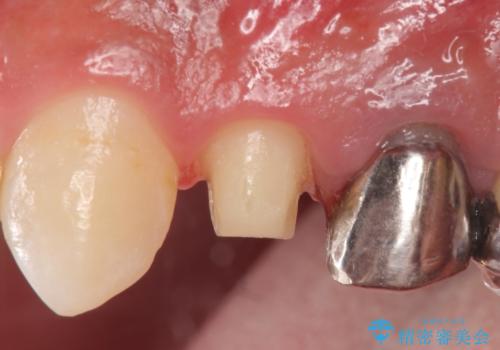

診査の結果、左上4番目の歯の神経が死んでおり、根尖に膿が溜まっていることが原因とわかりました。

そのため左上4番目の歯は根管治療を行い、歯茎の膿の出口の消失を確認後、オールセラミッククラウンによる補綴を行いました。